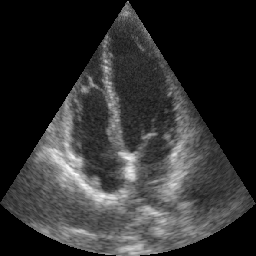

Transthoracic echo is one of the most common means of cardiac studies in the clinical routines. During the echo exam, the sonographer captures a set of standard cross sections (echo views) of the heart. Each 2D echo view cuts through the 3D cardiac geometry via a unique plane. Consequently, different views share some limited information. In this work, we investigate the feasibility of generating a 2D echo view using another view based on adversarial generative models. The objective optimized to train the view-conversion model is based on the ideas introduced by LSGAN, PatchGAN and Conditional GAN (cGAN). The size and length of the left ventricle in the generated target echo view is compared against that of the target ground-truth to assess the validity of the echo view conversion. Results show that there is a correlation of 0.50 between the LV areas and 0.49 between the LV lengths of the generated target frames and the real target frames.